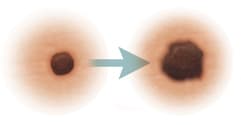

Evolving

|

When the mole changes in the way it looks over time